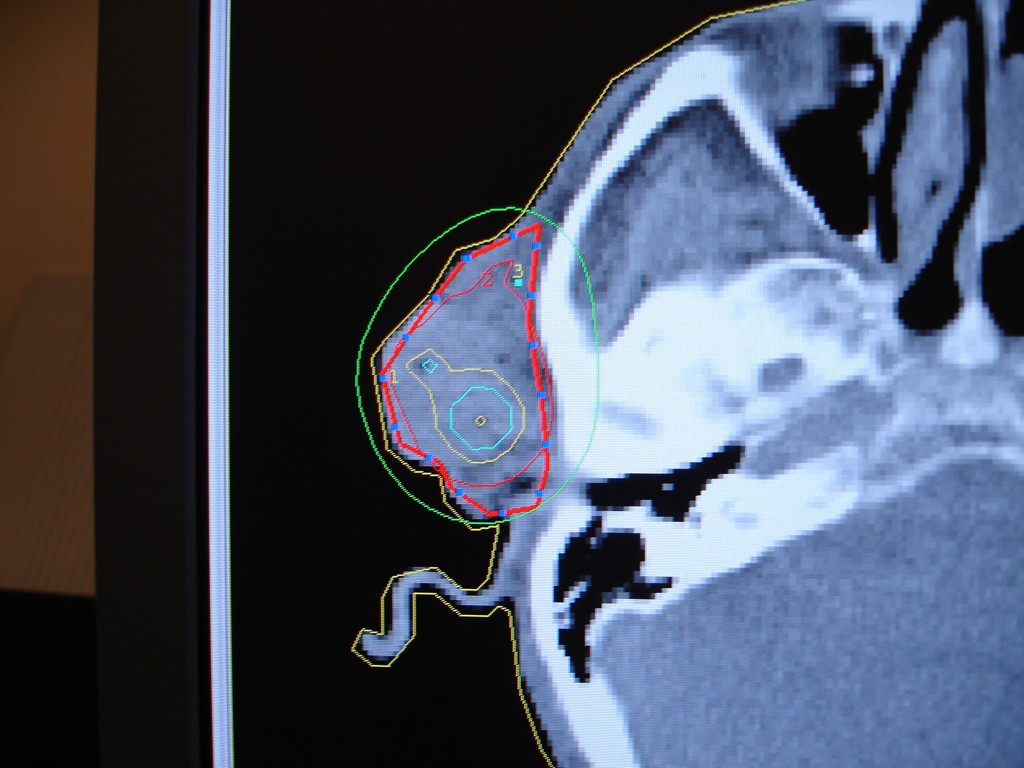

Zaawansowany rak skóry twarzy okolicy przedusznej. Zastosowano brachyterapię HDR, podano 10 frakcji po 5 Gy, raz dziennie. W znieczuleniu miejscowym założono 5 aplikatorów śródtkankowych elastycznych.

Planowanie leczenia - skan TK, wrysowany CTV (Clinical Target Volume), widok izodoz